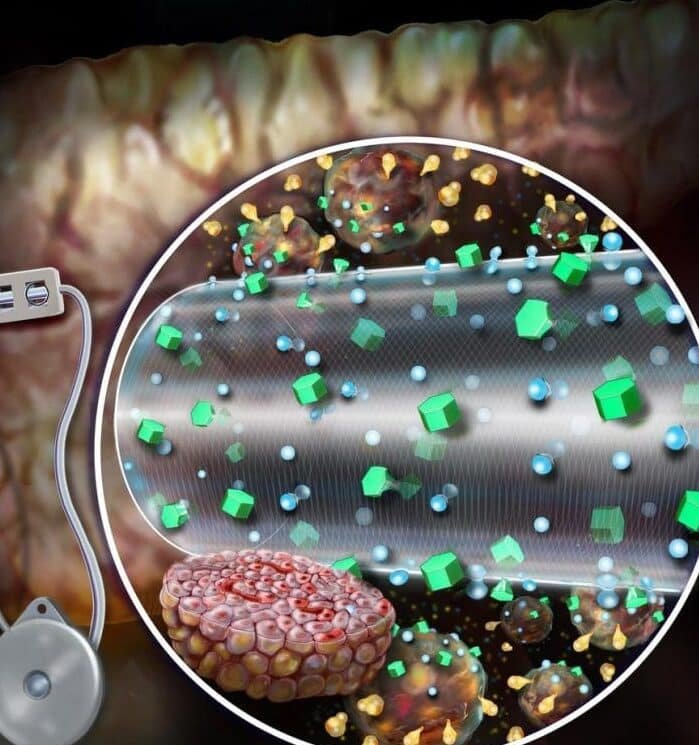

representa un avance revolucionario en el tratamiento de la diabetes, ofreciendo una alternativa prometedora a las terapias...

Los stents biodegradables que desaparecen tras curar la arteria representan un avance revolucionario en el tratamiento de...